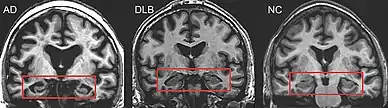

PET or SPECT imaging can be used to detect reduced dopamine transporter uptake and distinguish AD from DLB.[57][149] Severe atrophy of the hippocampus is more typical of AD than DLB.[150] Before dementia develops (during the mild cognitive impairment phase), MRI scans show normal hippocampal volume. After dementia develops, MRI shows more atrophy among individuals with AD, and a slower reduction in volume over time among people with DLB than those with AD.[33] Compared to people with AD, FDG-PET brain scans in people with DLB often show a cingulate island sign.[33]

Direct laboratory-measurable biomarkers for DLB diagnosis are not known, but several indirect methods can lend further evidence for diagnosis.[25] The indicative diagnostic biomarkers are: reduced dopamine transporter uptake in the basal ganglia shown on PET or SPECT imaging; low uptake of 123iodine-metaiodobenzylguanidine (123I-MIBG) shown on myocardial scintigraphy; and loss of atonia during REM sleep evidenced on polysomnography. Supportive diagnostic biomarkers (from PET, SPECT, CT, or MRI brain imaging studies or EEG monitoring[124]) are: lack of damage to medial temporal lobe (damage is more likely in AD[116]); reduced occipital activity; and prominent slow-wave activity on EEG.[25]